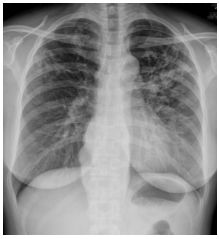

9.CC: 咳嗽 4 周,有痰